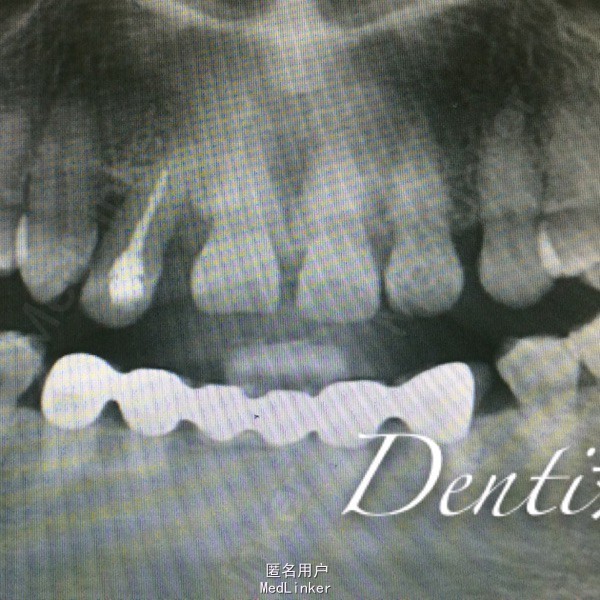

专科检查:口腔卫生一般,前牙扇形打开,散在间隙,开 牙合 ,右上2牙体完整,远中颊侧移位,松动I度,牙龈退缩4—6mm,未探及深牙周袋 辅助检查:X线片示,右上2牙槽骨退缩至根尖1/3,根管恰充填

诊断:牙周炎 处置:右上树脂充填,改形修复